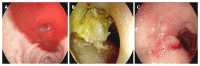

Methods: In our retrospective study we took into account 579 out of 1177 patients receiving endoscopic treatment for NV-UGIB admitted to our institution from 2008 to 2015; the remaining 598 patients were treated with other treatments. Initial hemostasis was not achieved in 45 of 579 patients; early rebleeding occurred in 12 of 579 patients. Thirty-three patients were treated with modified cyanoacrylate: 27 patients had duodenal, gastric or anastomotic ulcers, 3 had post-mucosectomy bleeding, 2 had Dieulafoy's lesions, and 1 had duodenal diverticular bleeding.

Results: Of the 45 patients treated endoscopically without initial hemostasis or with early rebleeding, 33 (76.7%) were treated with modified cyanoacrylate glue, 16 (37.2%) underwent surgery, and 3 (7.0%) were treated with selective transarterial embolization. The mean age of patients treated with NBCA + MS (23 males and 10 females) was 74.5 years. Modified cyanoacrylate was used in 24 patients during the first endoscopy and in 9 patients experiencing rebleeding. Overall, hemostasis was achieved in 26 of 33 patients (78.8%): 19 out of 24 (79.2%) during the first endoscopy and in 7 out of 9 (77.8%) among early rebleeders. Two patients (22.2%) not responding to cyanoacrylate treatment were treated with surgery or transarterial embolization. One patient had early rebleeding after treatment with cyanoacrylate. No late rebleeding during the follow-up or complications related to the glue injection were recorded.